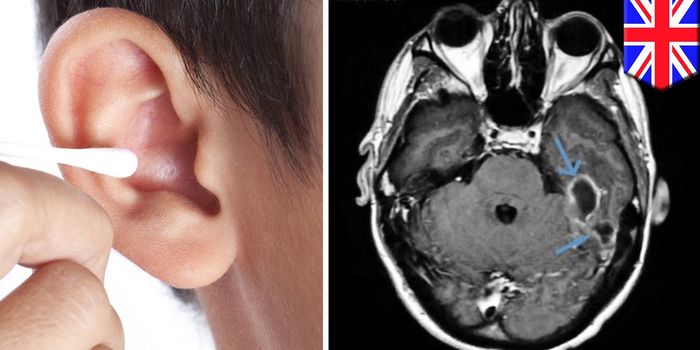

MAR 20, 2019VideosA 31-year-old British man had to go to the hospital after getting an infection in his ear that spread to the lining of h ...

APR 27, 2018Clinical & Molecular DXSimply looking out for the classic warning signs of a meningococcal infection may cause some cases to go unnoticed - at ...